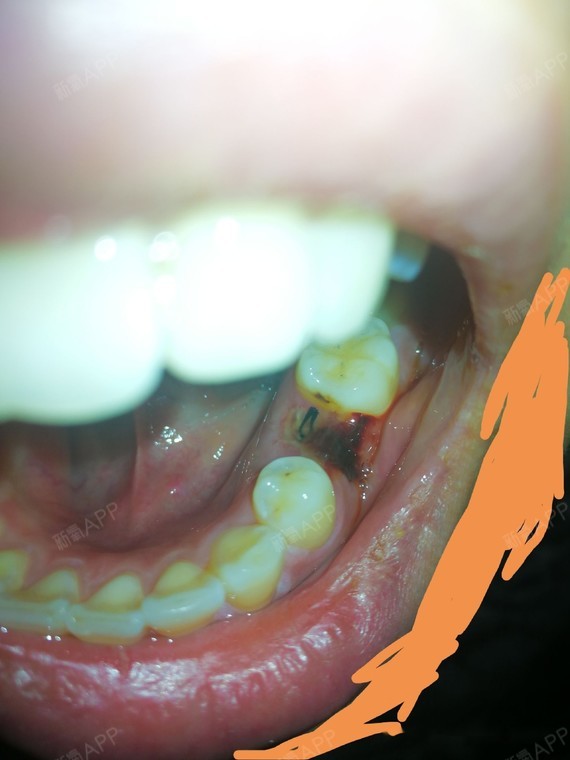

牙齿快要烂掉了医生却说不能拔牙

图片尺寸460x459